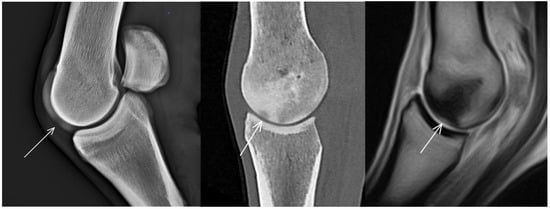

| Hypoattenuating lesion in the dorsal subchondral bone Subchondral bone thickening Dorsal/palmar half Increased attenuation in the trabecular bone Dorsal/palmar half Cone shaped/patchy Focal separated hyperattenuation | Hyperintense signal in the dorsal subchondral bone Subchondral bone thickening Dorsal/palmar half Decreased signal intensity in the trabecular bone Dorsal/palmar half Cone shaped/patchy Focal separated intermediate/low signal intensity | Radiolucent lesion Subchondral bone thickening Dorsal Increased trabecular bone opacity | |

| Proximal phalanx Sagittal groove | |||

| Subchondral bone thickening Dorsal/middle/palmar third Increased attenuation in the trabecular bone Hypoattenuating lesion in the subchondral bone Location | Subchondral bone thickening Dorsal/middle/palmar third Decreased signal intensity in the trabecular bone Increased signal intensity in the subchondral bone Location | Subchondral bone thickening Increased opacity in the trabecular bone Lucent lesion in the subchondral bone Location | |